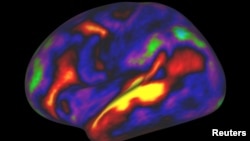

The regions were mapped based on features such as cortical thickness and the amount of insulation, called myelin, around nerve-cell connections.

The researchers also used MRI data on cortical activity when people carry out tasks such as listening to stories, computing math problems and looking at other people making various facial expressions.